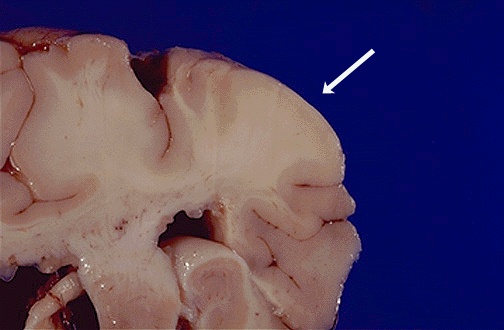

| Here is another tuber with tuberous sclerosis. The distinction between grey and white matter is lost. These patients can also have cardiac rhabdomyomas, renal angiomyolipomas, adenoma sebaceum of the skin, and pancreatic cysts. [Image contributed by Jeannette J. Townsend, MD, University of Utah] |